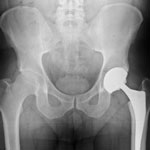

A plaintiff who filed a Zimmer hip lawsuit in the United States’ District Court for the District of Illinois and then later passed away was seeking compensation for the injuries she allegedly suffered related to the Zimmer Trilogy hip replacement system. Mary Jo Ott died at the age of 66 of causes unrelated to her hip replacement complications, and the executor of her estate, Jori A. Greybill, is continuing with the plaintiff’s lawsuit. The lawsuit holds device manufacturer Zimmer liable for the injuries the patient suffered after being implanted with one of their many hip replacement systems.

The judge concluded that this evidence was enough to preclude a summary judgment in the lawsuit and the case should continue as expected. Ott’s lawsuit is not the only one that has been filed against Zimmer in recent years–many plaintiffs have commenced litigation against the orthopedics manufacturer after experiencing problems related to hip replacement systems they have manufactured and marketed, but most of these lawsuits deal with the Durom Cup hip replacement system as opposed to the Trilogy, which is the device Ott had an issue with.

However, Ott is not the only one to have filed a lawsuit dealing with problems related to the Trilogy hip replacement system. A Texas man filed a lawsuit in January of last year claiming that within 15 months of being implanted with the Trilogy device, he began to experience complications. He, like Ott, eventually had to have revision surgery that would ultimately remove and replace the device in question.